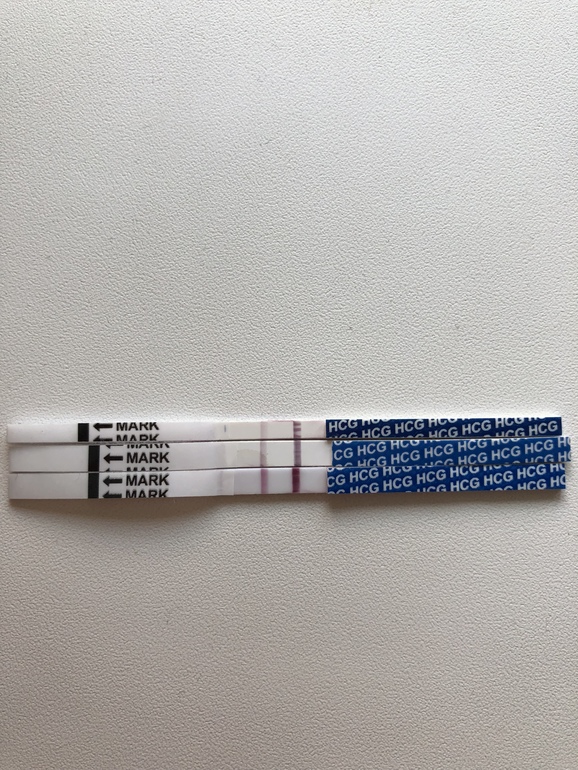

31 день цикла - сделала дешёвенький безымянный тест и на свет, через минут 10 увидела призрак призрака ( даже не фоткала, чтобы не разочароваться).

32 день, 33 день и 34 ниже на фото в ряд.

Больше тесты я не замачивала.